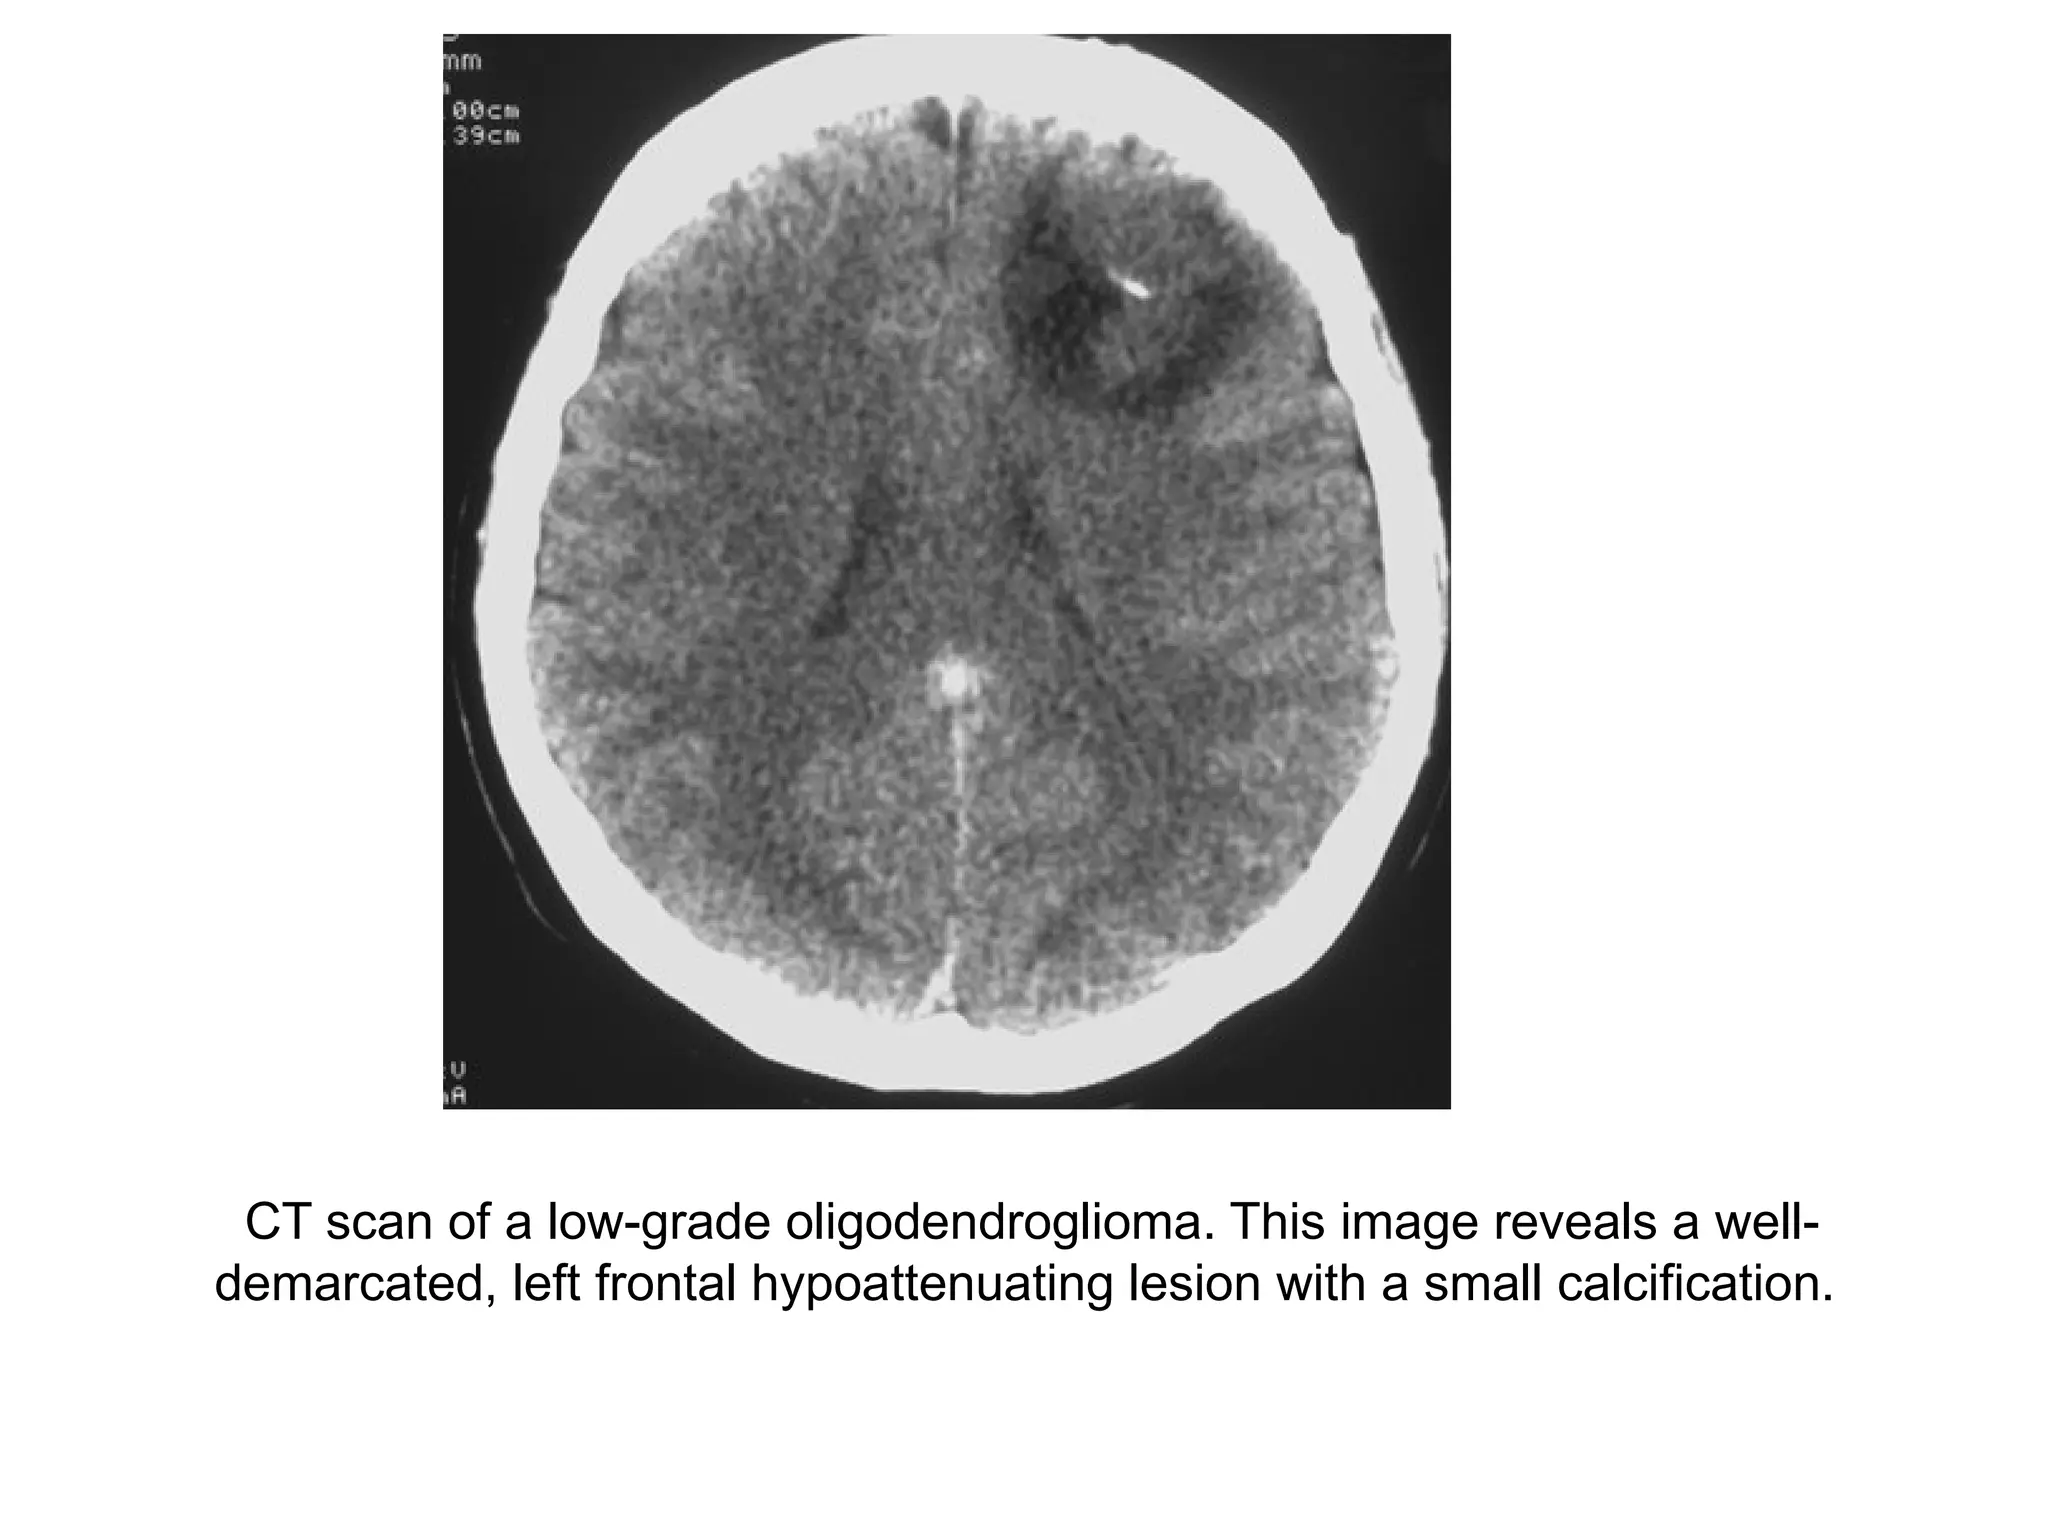

CT scan of a low-grade oligodendroglioma. This image reveals a well-

demarcated, left frontal hypoattenuating lesion with a small calcification.

The CT shows a mass with calcifications,

which extends all the way to the cortex.

Although this is a large tumor there is only

limited mass effect on surrounding

structures, which indicates that this is an

infiltrating tumor.

The most likely diagnosis is

oligodendroglioma.

The differential diagnosis includes a

malignant astrocytoma or a glioblastoma.